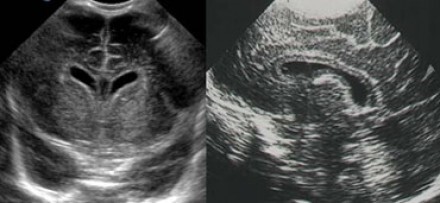

Neonatology Cavum Septum Image